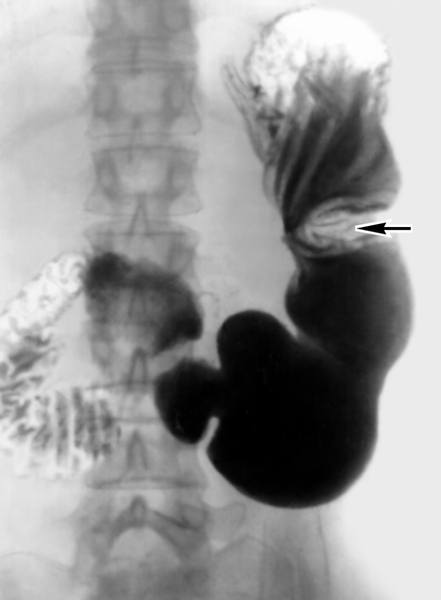

Симптом ‘ниши’ при язвенной болезни желудка

Рентгенография желудка с контрастом — Методика в настоящее время несколько устарела. Суть ее заключается в следующем: больной выпивает контрастную бариевую смесь. Затем врач-рентгенолог проводит ряд снимков, которые показывают, как продвигается контраст по слизистой. Картина язвенного дефекта обычно описывается как «симптом ниши».